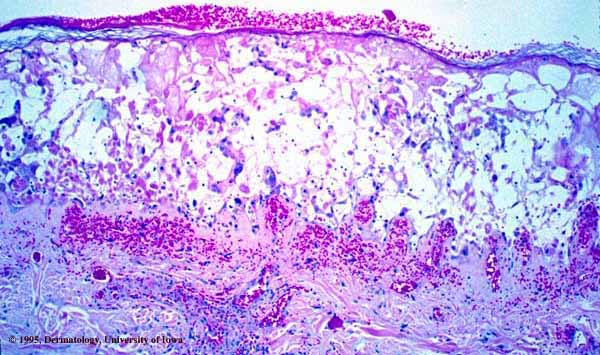

Herpes simplex = العقبول البسيط